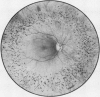

Intermediate sex-linked inheritance.